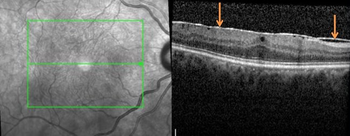

Il s’agit de l’apparition spontanée d’une fine membrane à la surface de la rétine, pouvant entraîner sa déformation et altérer la vision des détails.

Le traitement consiste en une vitrectomie avec pelage de la membrane épirétinienne.